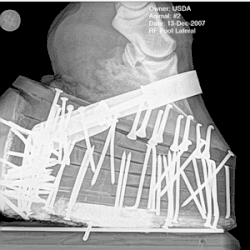

Performance horses, sometimes called "padded" or "built up", exhibit flashy and animated gaits, lifting their forelegs high off the ground with each step.[25] This exaggerated action is sometimes called the "Big Lick".[26] The customary style for rider attire and tack is saddle seat. Horses are shod in double and triple-nailed pads,[25] which are sometimes called "stacks".[27] In the early 21st century, this form of shoeing is now prohibited at shows governed by the National Walking Horse Association (NWHA),[22]: 3 and the United States Equestrian Federation (USEF).[28] Artificially set tails are seen in "performance" classes, on full-grown horses in halter classes, and in some harness classes, but generally are not allowed in pleasure or flat-shod competition.[24]: 12

Action devices, which remain legal but are often used in conjunction with illegal soring practices,[27] are defined in the Code of Federal Regulations as "any boot, collar, chain, roller, or other device which encircles or is placed upon the lower extremity of the leg of a horse in such a manner that it can either rotate around the leg, or slide up and down the leg so as to cause friction, or which can strike the hoof, coronet band or fetlock joint".[32]

Between 1978 and 1982, Auburn University conducted research as to the effect of applications of chemical and physical irritants to the legs of Tennessee Walking Horses. The study found that chains of any weight, used in combination with chemical soring, produced lesions and pain in horses. However, chains of 6 ounces or lighter, used on their own, produced no pain, tissue damage or thermographic changes.[33]